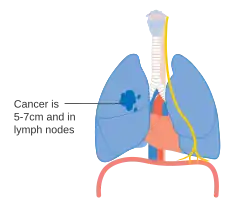

De stadiëring van niet-kleincellige longkanker (NSCLC) vindt in eerste instantie plaats aan de hand van de TNM-classificatie 8ste editie. Deze is gebaseerd op de grootte van de primaire tumor, verspreiding naar lymfeknopen (nodes) en metastasen (uitzaaiingen). Vervolgens wordt op basis van de TNM-parameters de kanker in een groep ingedeeld, die kan variëren van "occulte kanker" (kanker waar de primaire tumor nog niet gevonden is) tot de stadia 0, IA, IB, IIA, IIB, IIIA, IIIB en IV. Deze indeling in een stadiumgroep helpt bij de keuze van behandeling en het inschatten van de prognose.[43] Kleincellig longkanker (SCLC) wordt vanouds geclassificeerd als 'beperkt stadium' (beperkt tot één helft van de borst en binnen het bereik van één enkel verdraagbaar radiotherapieveld) of 'uitgebreide stadium' (verspreide ziekte).[2] De TNM-classificatie en -groepsindeling zijn echter nuttig bij het inschatten van de prognose.[43]

- Schema van belangrijkste kenmerken van longkanker stadiëring

Stadium IIB longkanker -

Een mogelijkheid voor stadium IIB-longkanker, T2b. Indien de tumor zich op 2 cm of minder van de carina bevindt, is het een stadium III -